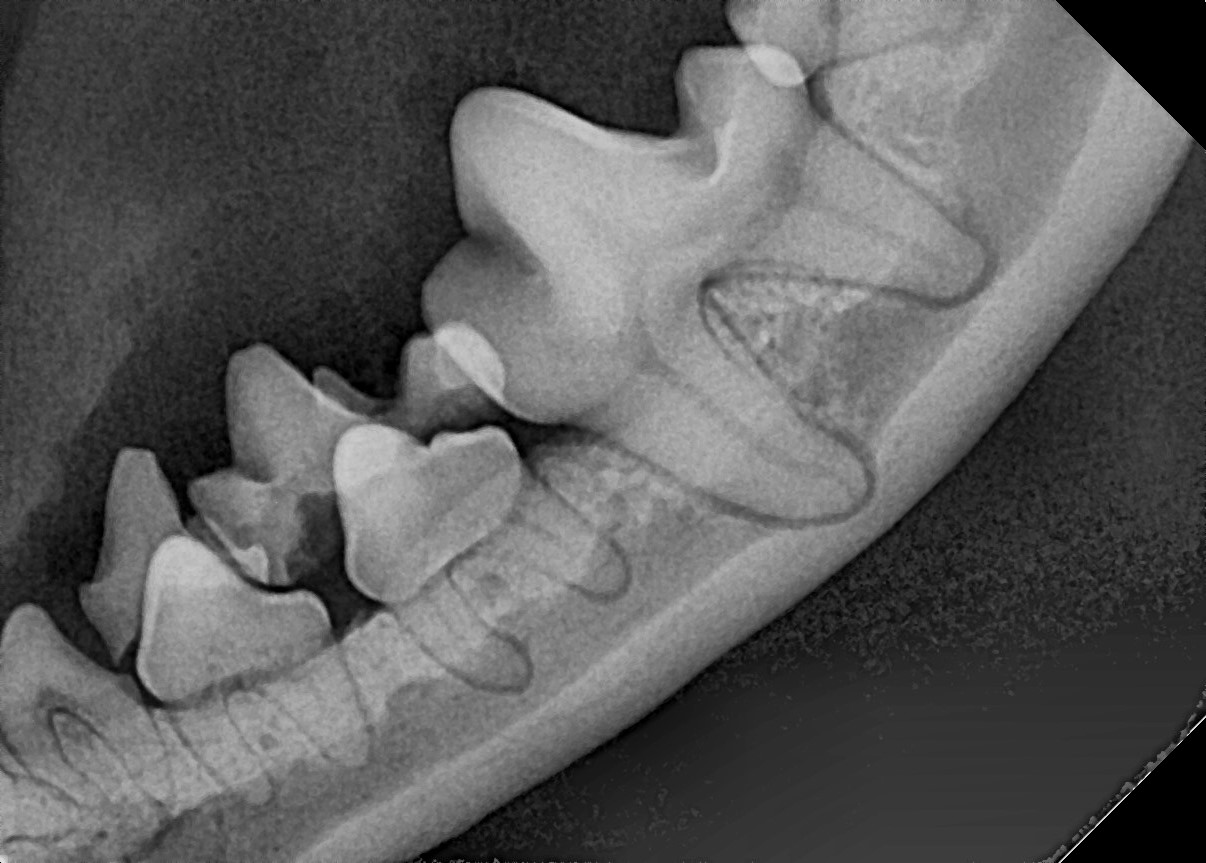

잔존 유치가 탈락되지 않아 영구치가 치아 사이에 같혀 있음 위 사진은 유치가 제때 탈락되지 않아 영구치가 세 번째 앞니 아래에 갇혀 있는 것을 보여줍니다.

세 번째 앞니도 송곳니 간섭으로 인해 정상위치 보다 위쪽으로 벗어나 있는 것(deviation)을 확인할 수 있습니다.

잔존 유치를 제거해 주었더니 별다른 교정 장치를 사용하지 않았음에도 2주 후 제위치로 이동하고 있는 송곳니를 확인할 수 있습니다.